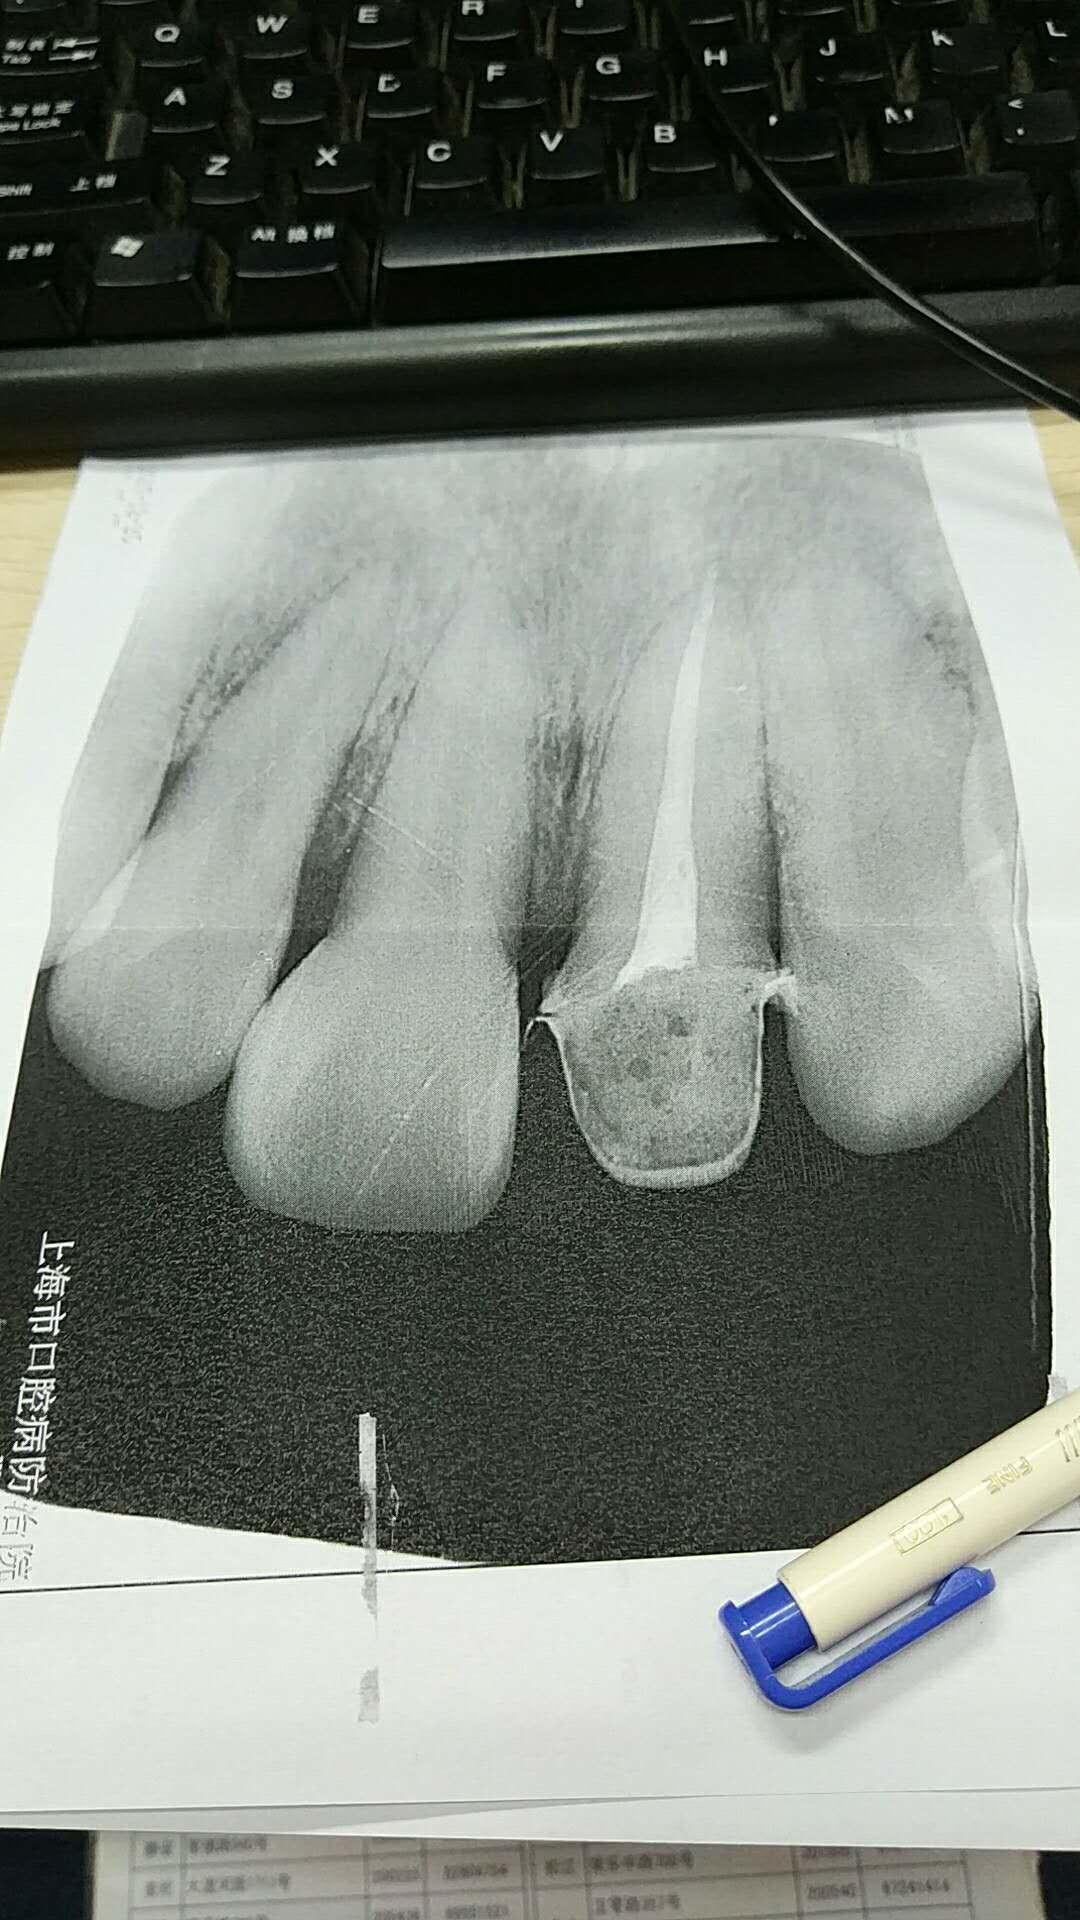

左上前牙根尖周炎一例

图片尺寸680x332